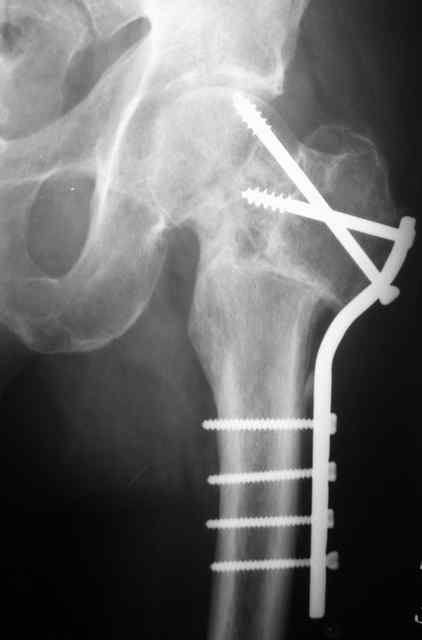

К сожалению, социальный статус пациента не восстановится ни после остеосинтеза, ни после ТЭП, в армии его уже не оставят. Склоняюсь к варианту медиализирующей остеотомии. С 90-х годов при недоступности основной массе платного эндопротезирования и невозможности три года ожидания квоты пациентам с несросшимися переломами ШБК мы делали вальгирующую чрезвертельную остетомию с медиализацией и пациенты вполне довольны результатами.Осложнения минимальны, начальные аваскулярные дистрофии головки способны к регрессу при соблюдении пациентом режима нагрузки. Очень привлекательно выглядит схема остеотомии с латерализацией удлиняющая шейку, описанная раннее на форуме Д.Кульджановым, но ее пока не выполняли.

Прилагаю снимок пациента 69 лет оперирован лет 8 назад.